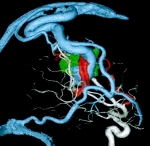

'19年5月

30代

富永/久貝

右中小脳脚 出血再発

SM 3(S1,E1,V1)

米国の病院

No.359 モニタリング

No.359 手術前

No.359 手術中

No.359 手術後

出血既往があり。2回の手術前血管内手術の後に、

Lateral transpeduncular approachにより再々出血予防を目的に

摘出手術を行う。完全摘出であることを確認した。

手術による合併症や後遺症なしで退院した。経過良好。